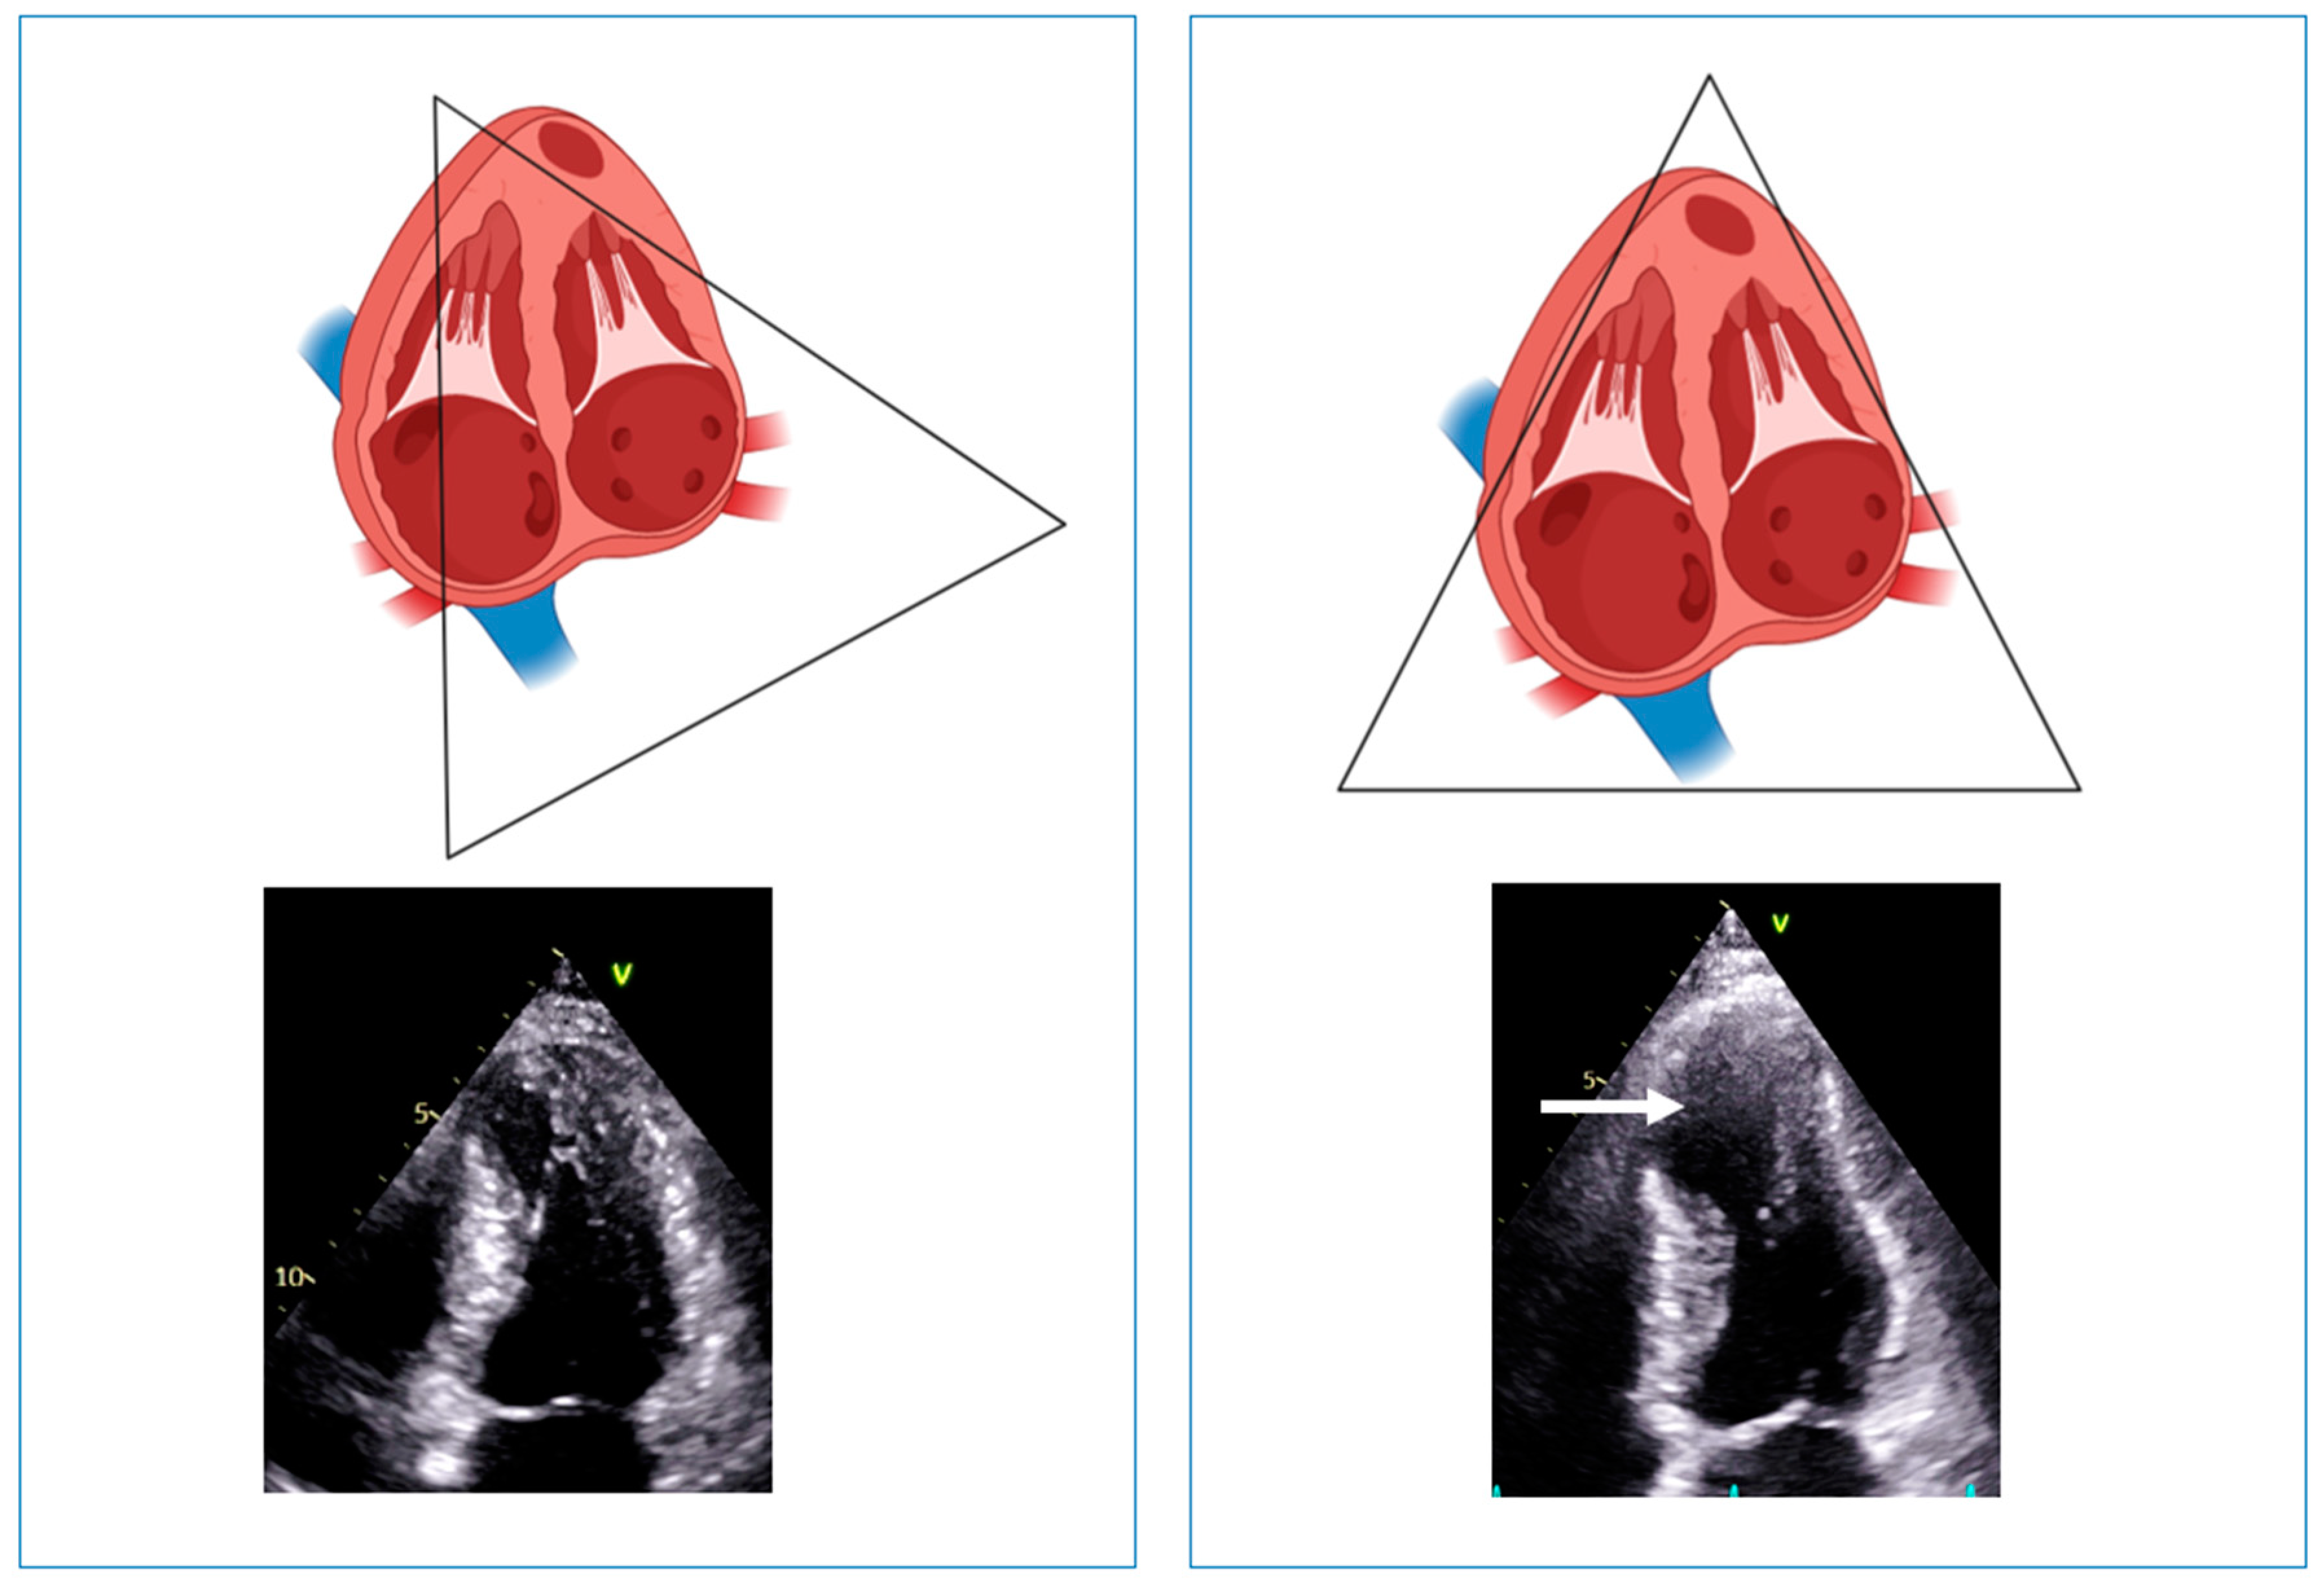

- Minami, Y.; Haruki, S.; Hagiwara, N. Phenotypic overlap in hypertrophic cardiomyopathy: Apical hypertrophy, midventricular obstruction, and apical aneurysm. J. Cardiol. 2014, 64, 463–469. [Google Scholar] [CrossRef]

- Matsubara, K.; Nakamura, T.; Kuribayashi, T.; Azuma, A.; Nakagawa, M. Sustained cavity obliteration and apical aneurysm formation in apical hypertrophic cardiomyopathy. J. Am. Coll. Cardiol. 2003, 42, 288–295. [Google Scholar] [CrossRef] [PubMed]

- Elsheshtawy, M.O.; Mahmoud, A.N.; Abdelghany, M.; Suen, I.H.; Sadiq, A.; Shani, J. Left ventricular aneurysms in hypertrophic cardiomyopathy with midventricular obstruction: A systematic review of literature. PACE 2018, 41, 7. [Google Scholar] [CrossRef]

- Minami, Y.; Kajimoto, K.; Terajima, Y.; Yashiro, B.; Okayama, D.; Haruki, S.; Nakajima, T.; Kawashiro, N.; Kawana, M.; Hagiwara, N. Clinical implications of midventricular obstruction in patients with hypertrophic cardiomyopathy. J. Am. Coll. Cardiol. 2011, 57, 2346–2355. [Google Scholar] [CrossRef]